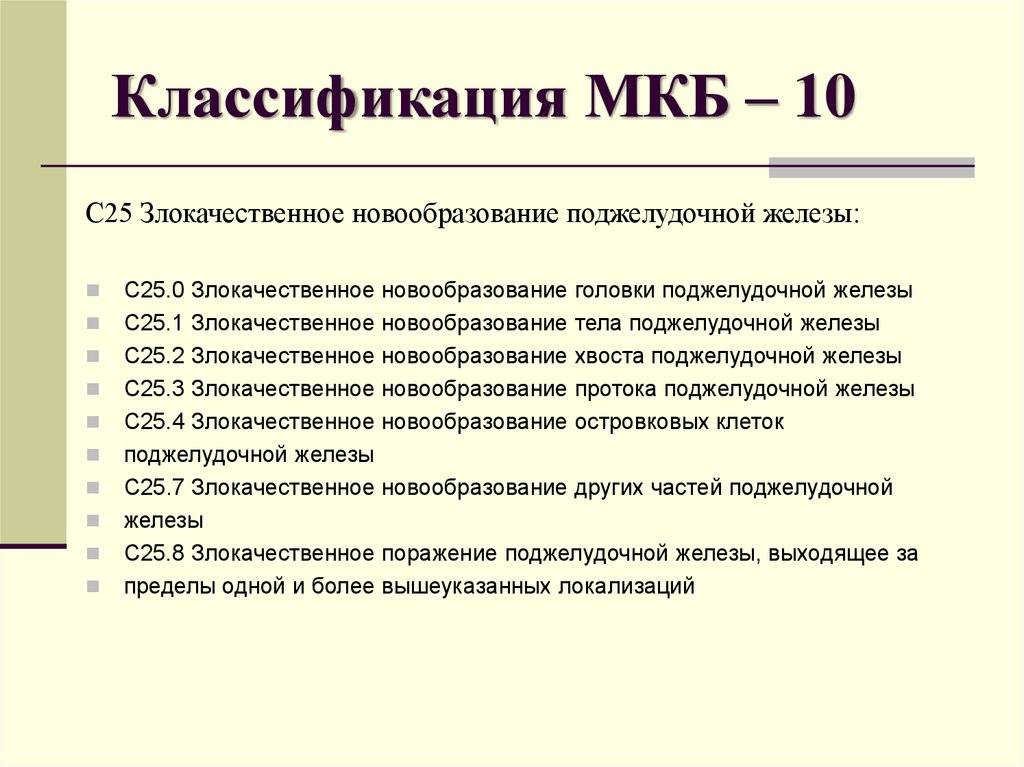

Код мкб 10 атерома головы

Код мкб 10 атерома головы 109 фото